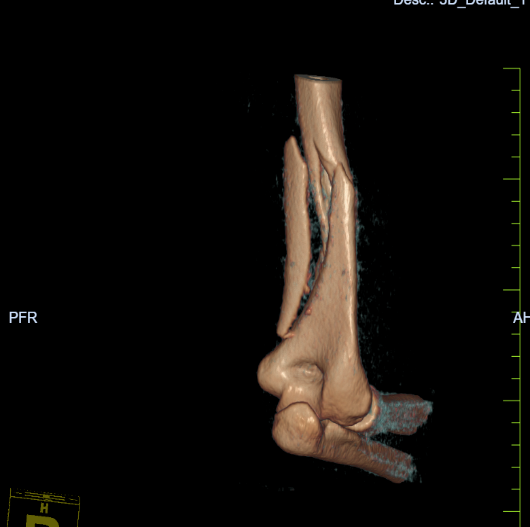

右肱骨干粉碎性骨折 术前X线片 右肱骨干粉碎性骨折 术前三维CT